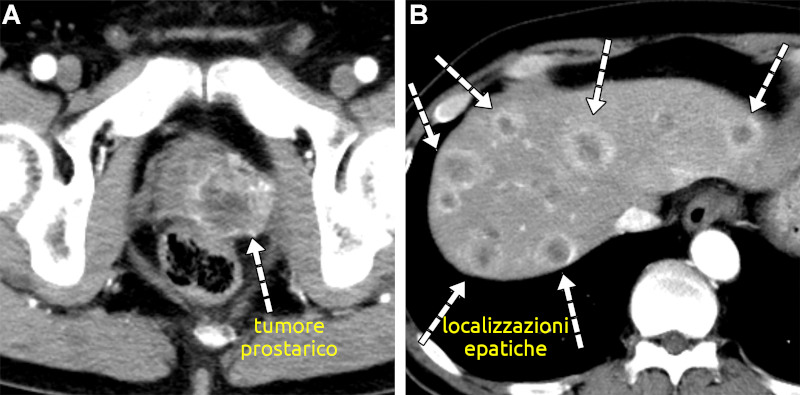

Metastasi epatiche

- Descrizione: Cancro del Fegato che compare dopo un altro cancro verificatosi in altra parte del corpo (principalmente intestino ed altri organi endodermici) o altra parte del fegato.

La presenza di una sola localizzazione ha a che fare con una specifica persona, mentre se le localizzazioni sono multiple, ha a che fare con se' stessi.